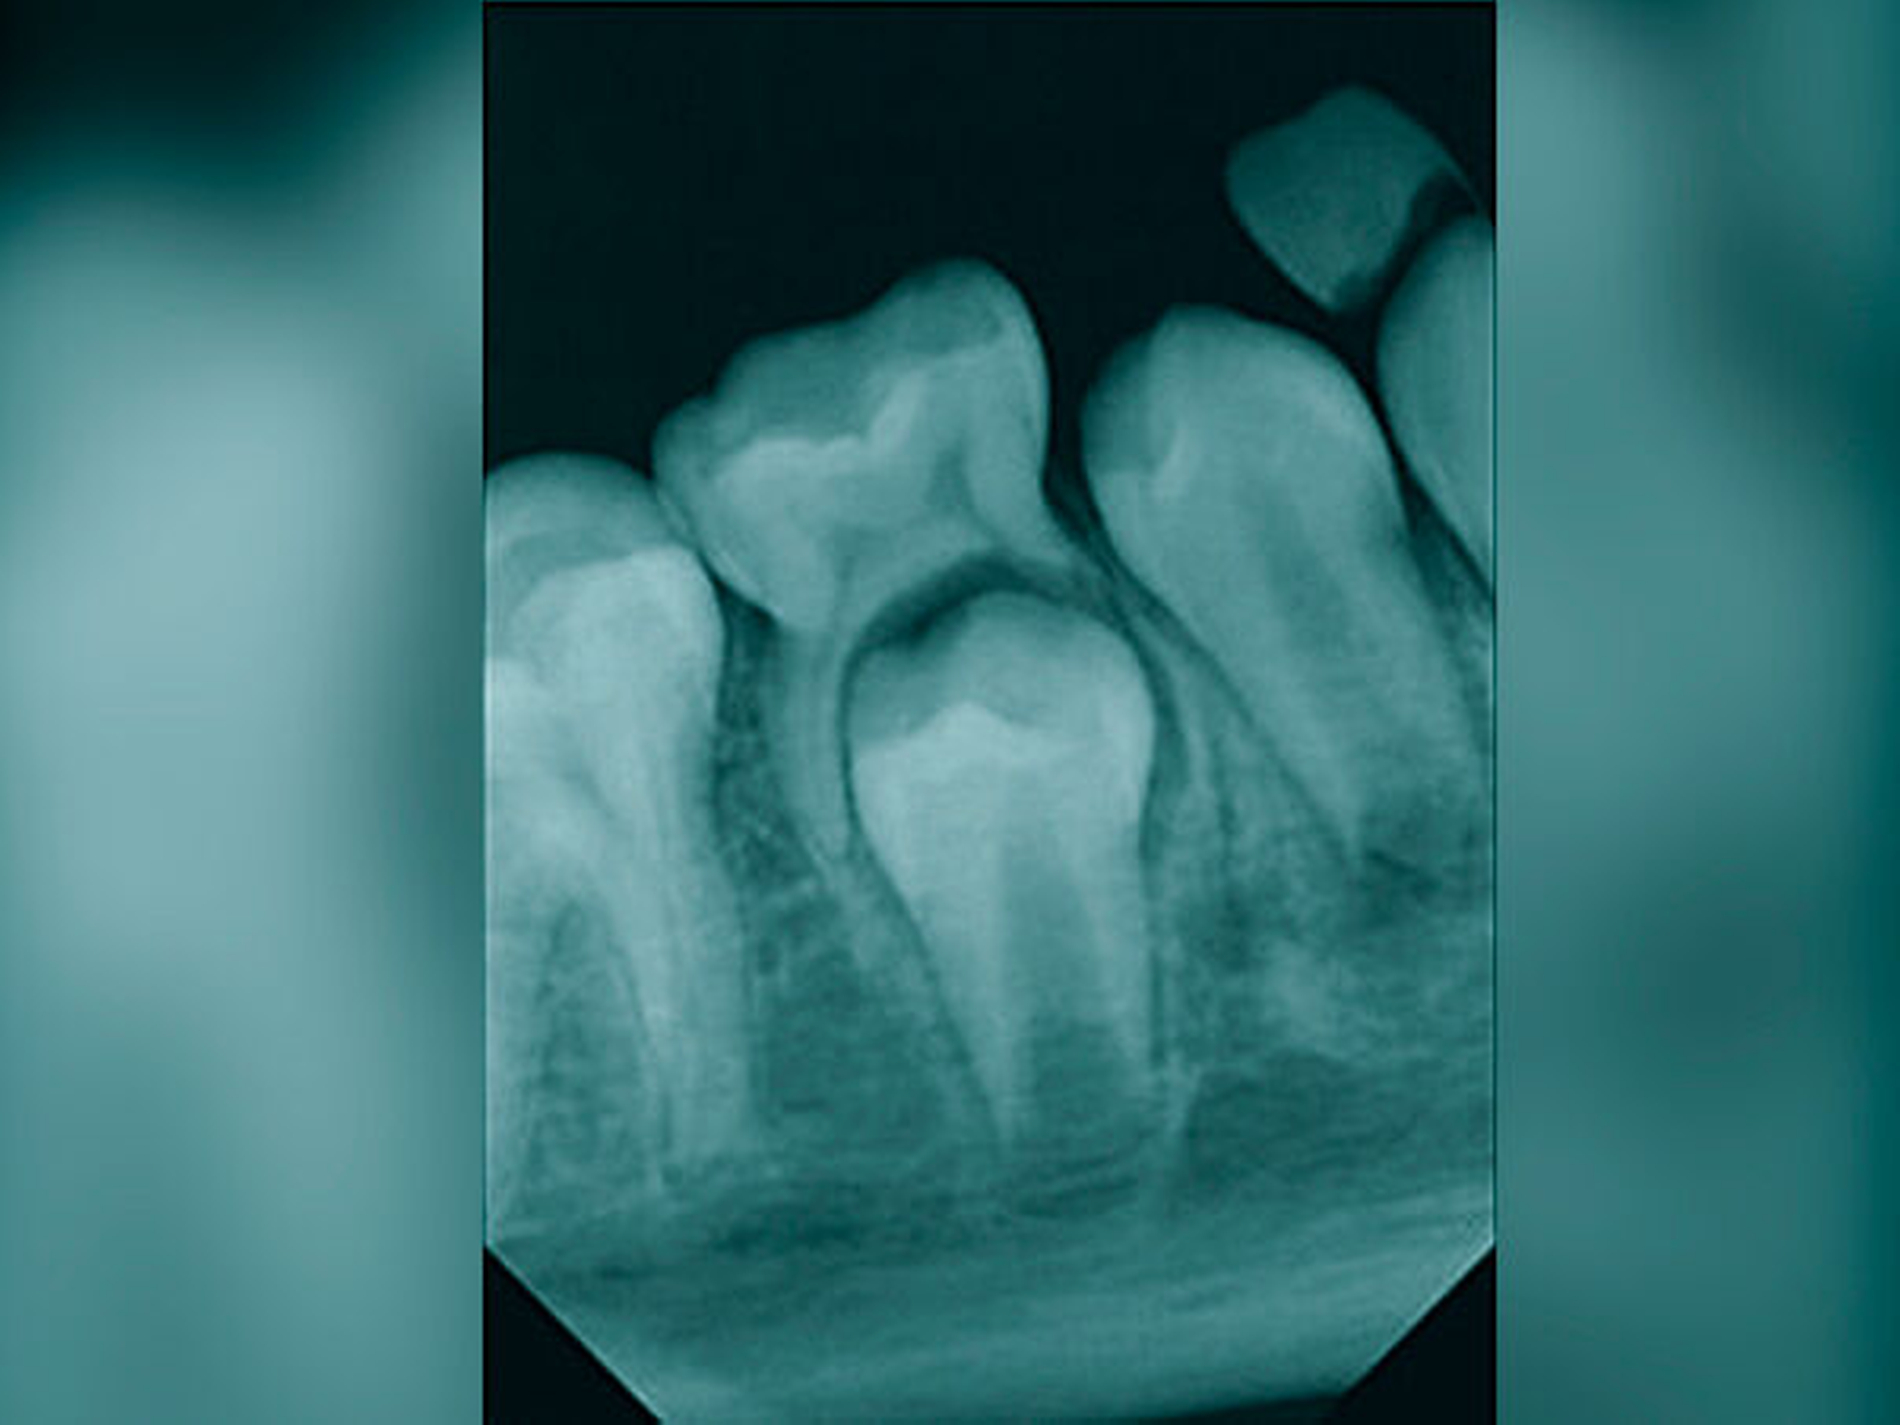

In der Regel sollte bei einem Frontzahnverlust im Oberkiefer ein Prämolar mit einer Wurzel verwendet werden. Die Wurzel einwurzeliger Prämolaren und deren Form sind in einer Schneidezahnalveole passfähiger und geeigneter für die parodontale Regeneration als ein Prämolar mit zwei Wurzeln. Der Prämolar sollte nach Möglichkeit aus dem Unterkiefer entnommen werden, da bei einem Misserfolg zwei Zähne innerhalb eines Kiefers fehlen würden. In der Regel wird die Extraktionslücke kieferorthopädisch mittels skelettaler Verankerung geschlossen. Zuvor ist die Anlage des dritten Molaren im betreffenden Quadranten zu prüfen, der nach kieferorthopädischer Einstellung mit dem zweiten Molaren des Oberkiefers okkludiert.

Das Wurzelwachstum des Transplantats sollte zum Zeitpunkt der Entnahme nicht mehr als zwei Drittel betragen. Dies kann eine operative Freilegung notwendig machen (Abb. 3).